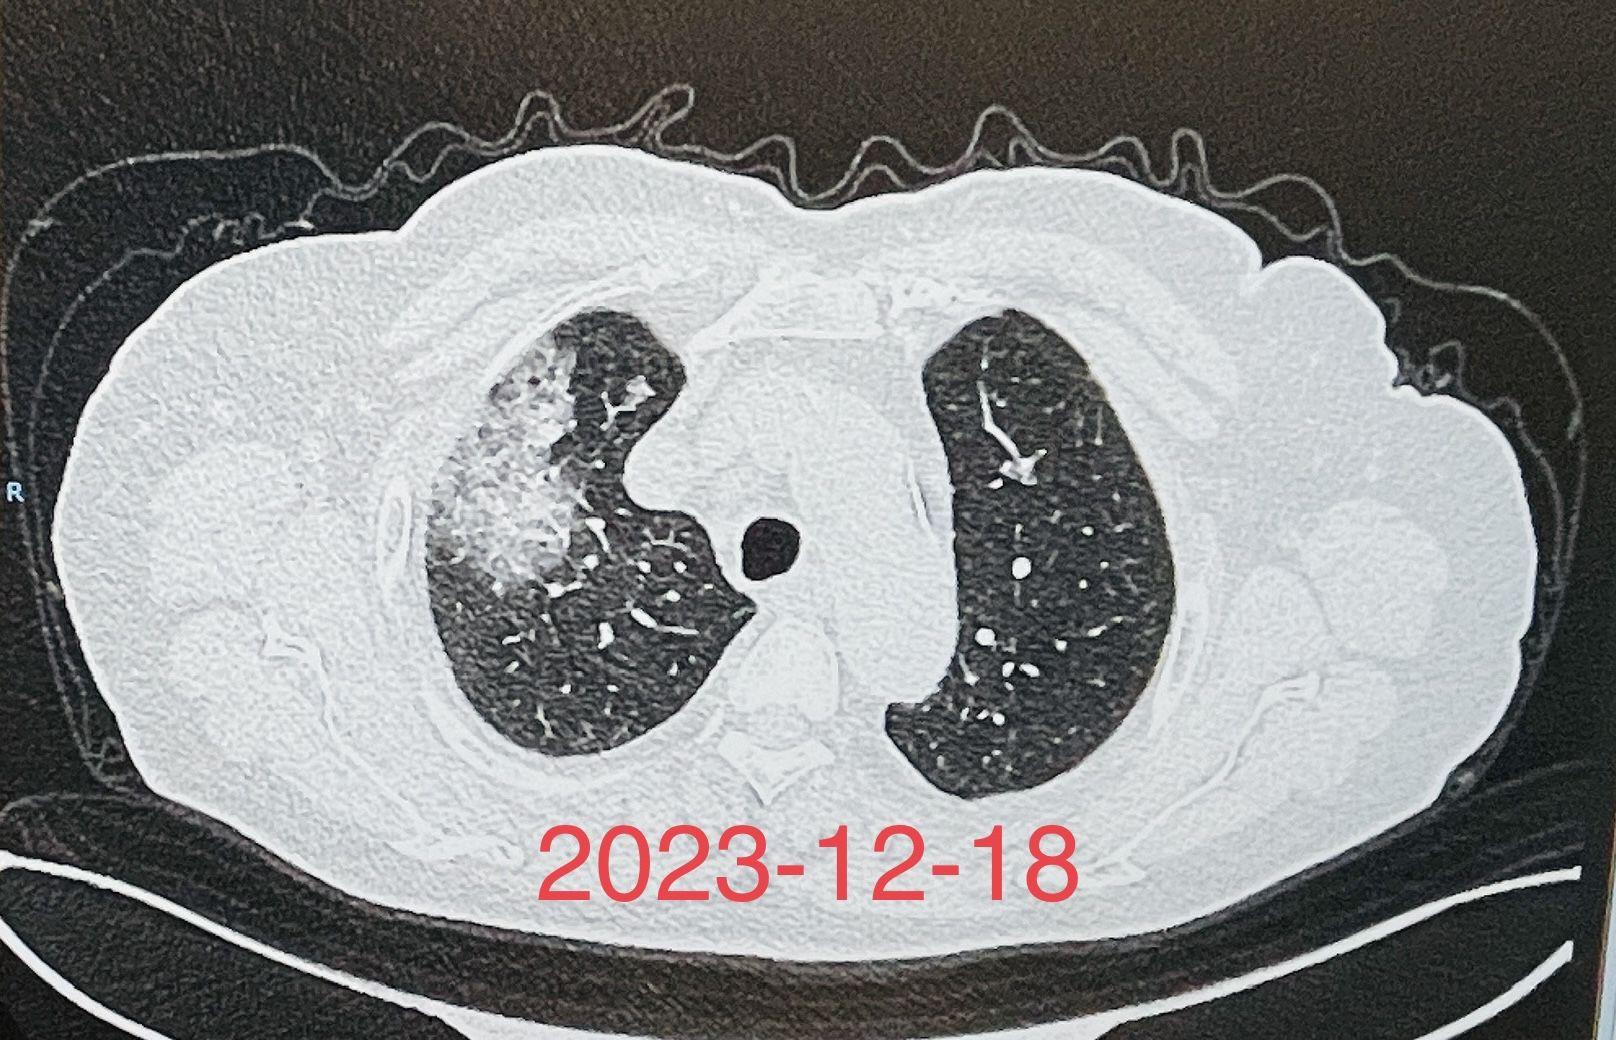

(图1)重症肺炎患者床旁气管镜检查及治疗前后的胸部X线片对比

这是收住呼吸RICU的一个混合感染,重症肺炎合并呼吸衰竭、心力衰竭的患者,经气管插管呼吸机辅助呼吸、床旁气管镜检查明确了病原菌,经积极有效的抗感染治疗,联合提高免疫、营养支持等综合治疗,以及呼吸重症监护室所有医护人员的精心护理,经积极抢救,患者的感染得到了有效控制,病情有了明显的改善。(图1)